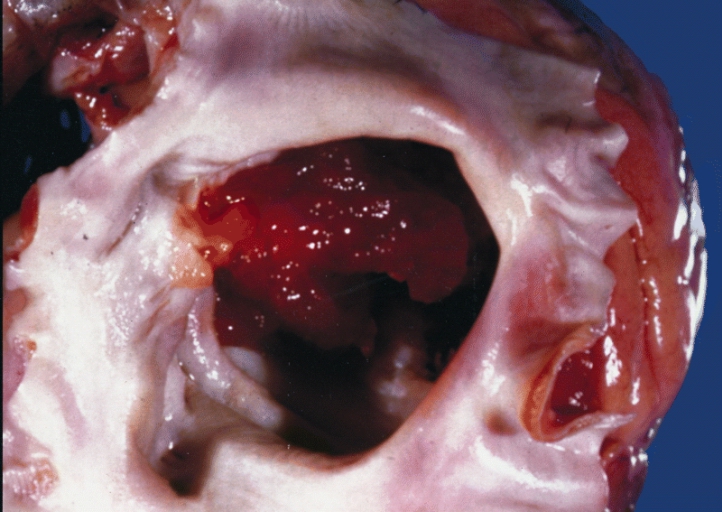

Myxoma

Myxomas are benign mesenchymal tumors.

Myxomas are the most common benign primary cardiac tumors.

Myxomas typically present with tachycardia or dyspnea on exertion.

Myxomas typically appear as pedunculated masses in the left atrium on imaging.

Myxomas may causes syncope by blockage the mitral valve.

Myxomas typically have a histologic appearance showing an abundance of ground substance and a gelatinous appearance.